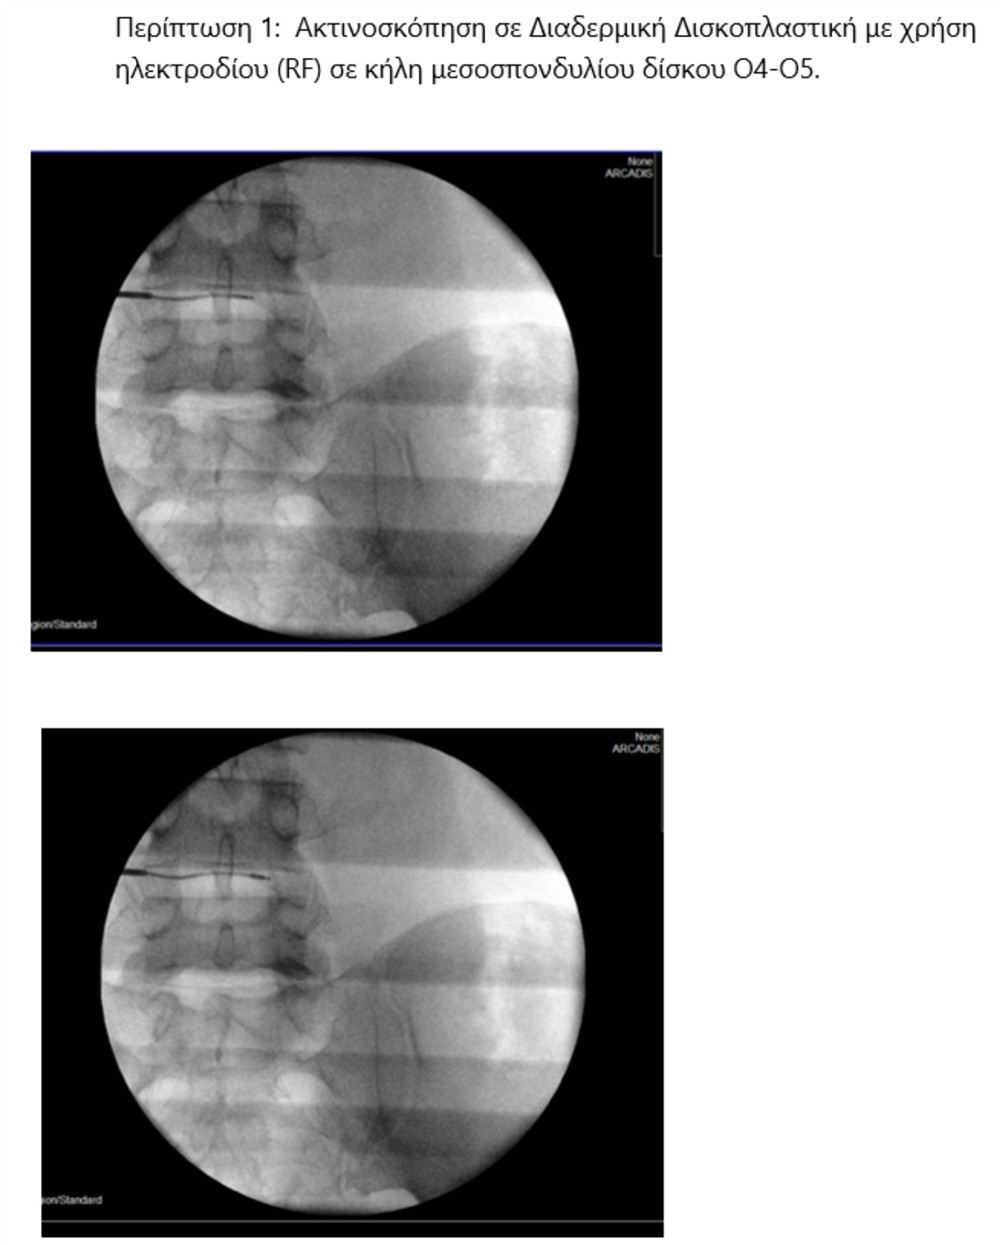

Χρησιμοποιώντας την εφαρμογή ραδιοσυχνοτήτων, εισάγεται, αρχικά, ένας οδηγός κάτω από ακτινοσκοπικό έλεγχο στον μεσοσπονδύλιο δίσκο και κατευθύνεται έμπροσθεν της κήλης. Μέσα από τον οδηγό εισάγεται ένα ηλεκτρόδιο, που η άκρη του έχει τη δυνατότητα κίνησης και στροφής 360? (Σχ. 1).